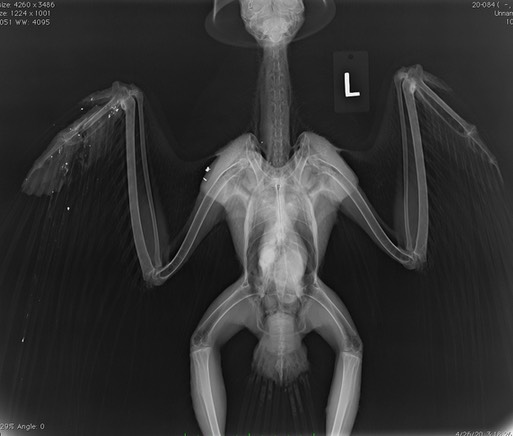

Swainson’s Hawk 20-084 had been shot. The white specks in the radiograph below stretch from the neck and shoulder to the wingtip.